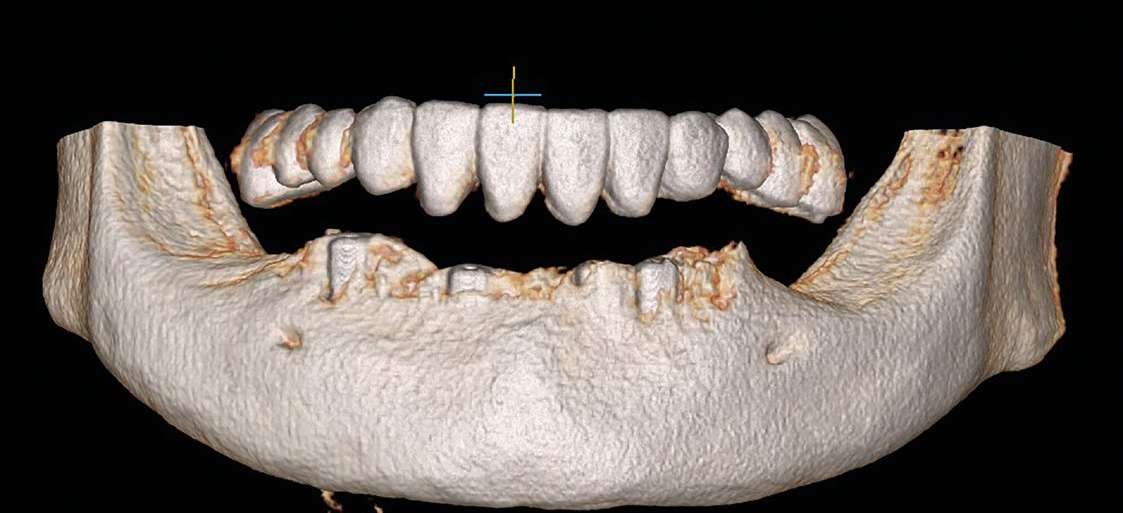

3. Análisis radiográfico y tomográfico (Ilustración 4):

 Constricción maxilar con deficiencia transversal

> 5 mm.

 Clase III esquelética.

 Patrón esquelético hiperdivergente con el plano oclusal mandibular compensado con rotación anti-horaria.

 Sutura palatina media parcialmente osificada (8) (9).

 Posición de terceros molares no favorable, por lo que se recomendó extracción.

Ilustración 4. Registros radiográficos iniciales de estudio.